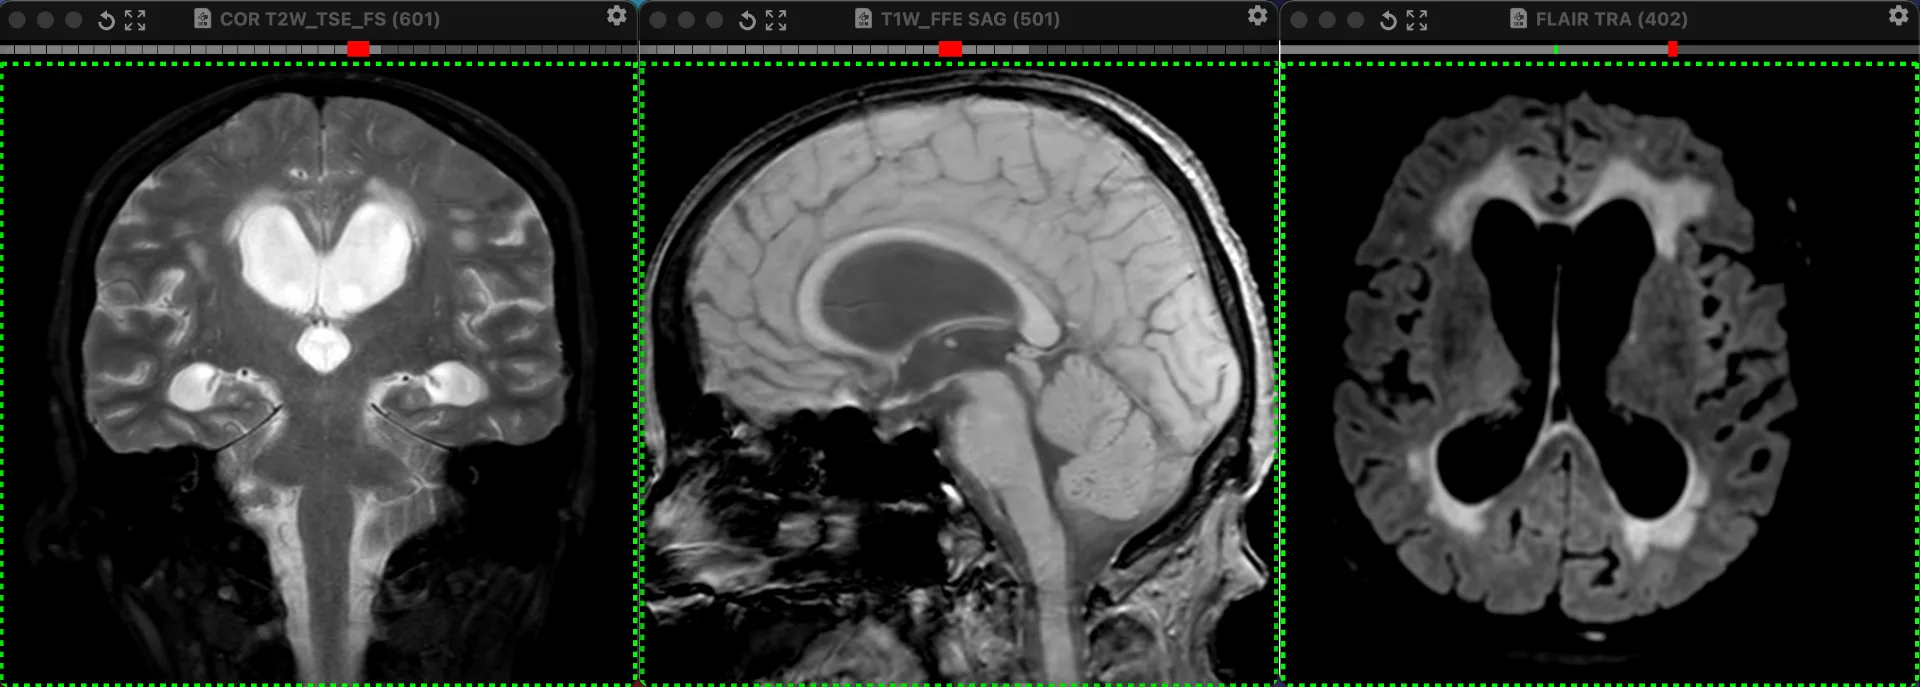

Наконец-то я увидел это воочию! Киста полости Верги, промежуточного паруса, осложнённая гидроцефалией. Из анамнеза: Низкое артериальнео давление, нарушение речи, затуманенное сознание, головная боль, головокружение, в 1989 году перенёс менингит.

А Вы видали такое? Я впервые вижу, раньше только читал в литературе.